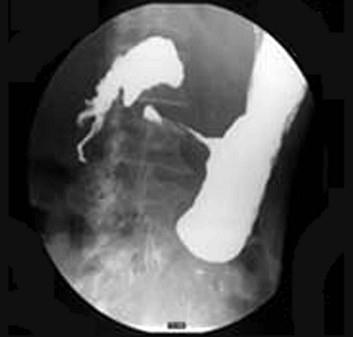

问题 女,56岁,上腹部钝痛、腹胀不适一月余,纳差、消瘦,影像检查如图,最可能的诊断是 ( )

选项 A、胃间质瘤 B、胃恶性间质瘤 C、胃腺癌并幽门狭窄 D、胃淋巴瘤 E、胃幽门管溃疡

答案 C